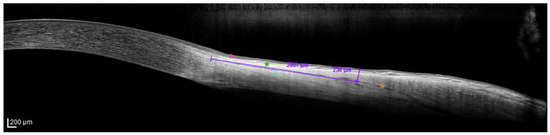

Intraoperative Use of a Topical Anesthetic Gel Versus Balanced Salt Solution During Cataract Surgery: Effects on Corneal Structure and Ocular Surface

J. Clin. Med. 2026, 15(5), 1992; https://doi.org/10.3390/jcm15051992 - 5 Mar 2026

Background/Objectives: During cataract surgery, topical anesthesia is routinely achieved through the instillation of topical anesthetic eye drops, while different agents may be applied to the corneal surface during the procedure to support lubrication and protection. The impact of these intraoperative strategies on corneal [...] Read more.

Background/Objectives: During cataract surgery, topical anesthesia is routinely achieved through the instillation of topical anesthetic eye drops, while different agents may be applied to the corneal surface during the procedure to support lubrication and protection. The impact of these intraoperative strategies on corneal integrity and postoperative ocular surface recovery remains an area of clinical interest. This study aimed to compare the intraoperative and postoperative effects of applying a topical anesthetic gel (Ophtesic, Horus Pharma) on the corneal surface versus the use of balanced salt solution (BSS) during cataract surgery. Methods: In this longitudinal, observational prospective study, 24 eyes of 24 patients undergoing phacoemulsification received either topical anesthetic gel (n = 15) or BSS irrigation (n = 9). Central corneal thickness (CCT) and epithelial thickness were measured preoperatively and on postoperative days 1, 5, and 15 using anterior segment optical coherence tomography (AS-OCT). Basal epithelial cell (BEC) density was assessed by in vivo confocal microscopy (IVCM), while OSDI score, non-invasive breakup time (NI-BUT), and Schirmer test I values were evaluated preoperatively and on postoperative days 5 and 15. Patient and surgeon satisfaction were rated using a Likert-like scale. Results: Both groups showed increased CCT and epithelial thickness at day 1. In the gel group, CCT returned to baseline by day 15 (p = 0.361), and epithelial thickness normalized by day 5 (p = 0.066). In the BSS group, CCT remained elevated at day 15 (p < 0.05), and epithelial thickness decreased at day 5 (p < 0.05) before returning to baseline. BEC density normalized at day 15 in the gel group (p = 0.107) but remained altered in the BSS group (p < 0.05). NI-BUT Schirmer I, and OSDI showed a trend toward faster recovery in the gel group than in the BSS group. Conclusions: In this exploratory study, intraoperative application of a topical anesthetic gel appeared to support early normalization of corneal and tear film parameters while providing effective anesthesia. Further studies are warranted to confirm these observations and evaluate potential long-term benefits. Full article